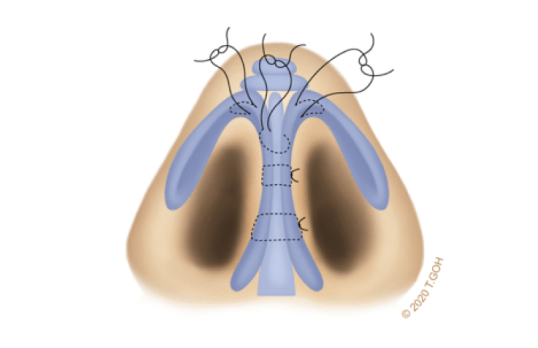

Use of Ear (Auricular) Cartilage Grafts

The ear is an ideal source of natural cartilage, offering soft yet durable material ideal for enhancing the nasal domes. This allows for the creation of a refined, well-defined tip.

The cartilage is carefully stacked and precisely stitched to shape and stabilise the tip, achieving the desired contours and a sophisticated appearance.

In cases of weak or widely splayed lower lateral cartilages, the nasal tip lacks support. Simple onlay grafting alone is insufficient, as the heavy tip may droop or lose shape over time. To address this, the tripod structure must be reinforced with sutures to create a stable tip. Columellar strut grafts may also be required to provide additional support.

A strong foundation is necessary to ensure the nasal tip retains its shape and position over time. By combining cartilage grafts with precise suture techniques, we create a stable nasal tip that is both durable and aesthetically refined.